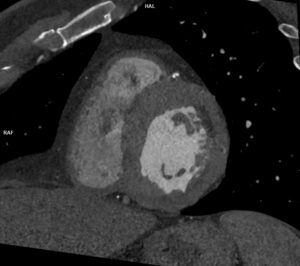

Figura 2: reconstrucție dinspre anterior de tip VRT crosa aortică la dreapta și diverticulul de origine a arterei subclavii stângi

Figura 3: reconstrucție dinspre posterior de tip VRT crosa aortică la dreapta și diverticulul de origine a arterei subclavii stângi

Discuţie caz nr 130: examinare efectuată pentru suspiciune de dilatație anevrismală a aortei ascendente; achiziția a fost realizată cu sincronizare ECG pentru vizualizare optimă a valvei aortice și a peretelui aortic și surpriza a fost un arc aortic la dreapta cu aortă descendentă toracică la dreapta și o dilatație anevrismală / diverticul posterior de trahee și esofag și anterior de coloana vertebrală din care are origine arteră subclavie stânga (Diverticulul Kommerell).

DE LUAT ACASĂ!!! Achiziția cu sincronizare ECG la examinarea AngioCT aortă toracică este indicat / obligatoriu sa fie utilizată la pacienții care sunt trimiși la examinare CT pentru evaluarea aortei toracice. Diverticulul Kommerell se referă de obicei la configurația bulboasă a originii unei artere subclaviculare stângi aberante în contextul unui arc aortic drept. Cu toate acestea, a fost descrisă inițial ca o protuberanță diverticulară la originea unei artere subclaviculare drepte aberante cu un arc aortic stâng și se observă și în arterele vertebrale drepte aberante (arteria lusoria vertebrală).